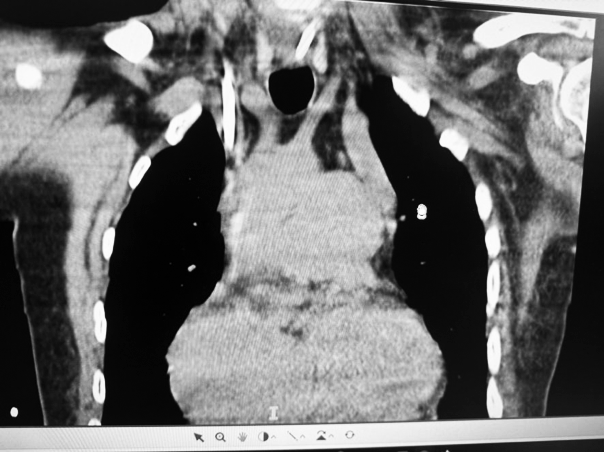

La TAC mostró una vena cava superior izquierda y otra derecha

Además de la anomalía vascular de la vena porta y de las cavidades cardíacas que presentes en este paciente, se detectó una anomalía vascular en las venas centrales. Se debe tener presente la posibilidad de que exista esta asociación de variantes anatómicas cuando debemos abordar vías centrales, en nuestro caso con catéter de doble lumen para tratamiento dialítico. El tip del catéter izquierdo se ubicó a nivel de seno coronario, donde el flujo sanguíneo resultó deficiente para efectuar el tratamiento dialítico. Se adjunta gráfico con esquema de las alteraciones más frecuentes de la vena cava superior doble.(1)